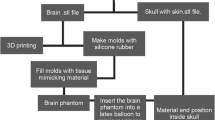

Our physical brain simulator combines 3D printing technologies to create the skull and moulds and 3D casting of tissue-mimicking silicone-based materials actually to manufacture the cerebral parenchyma, meningioma, and dura mater. In this first prototype, we assume the simplification of not including the arachnoid mater currently under investigation.

The manufacturing protocol is based on the 3D assembly of parenchyma and lesion models in a dedicated mould reproducing the skull morphology to which the dura mater is fixed, as shown in Fig. 55.5. While assembling the system, it is essential to keep the correct anatomical configuration and relative spatial features (i.e. mutual distances and positions between parenchymal and neoplastic structures and the meningeal membrane), to allow trainees to experience the same conditions they will find in actual clinical scenarios.

We manufactured the moulds for the cerebral parenchyma and meningioma using an 80–90 ShoreD and 65 MPa ultimate tensile strength hard photopolymer [61] with 0.1 mm layer resolution to create accurate and robust smooth surface finished parts.

Following initial tests, the rigid 3D-printed mould of the parenchyma was eventually replicated for process optimisation, producing a mask made of a soft, high viscosity, and fast-curing silicone (25 ShoreA), shown in Fig. 55.6. This choice improved both the ease of demoulding and the polymerisation quality at the surface boundaries.

We used two different silicone blends formulated in-house to manufacture these specific models as casting materials.

We moulded the meningioma using a poorly cross-linked tacky dielectric gel (10 Shore000 hardness), mixed with a 20% v/v 30 ShoreA platinum catalysed hardener with brittle properties, and coloured with white pigments. Additional liquid additives were employed to reduce surface tension (1.5% w/w) and lower the blend’s viscosity (10% v/v). We chose this formulation because we identified it as the most accurate to reproduce the dense texture of the meningioma, as shown in Fig. 55.7.

For the cerebral parenchyma, we chose a composite material made from 60% silicon oil and 40% silicone blend created using a poorly cross-linked tacky dielectric gel (10 Shore000 hardness), mixed with a 7.5% v/v room-temperature vulcanising (RTV) silicone rubber hardener (20 ShoreA) with brittle properties, and coloured with a mixture of white and light flesh-tone pigments. Additional liquid additives were employed both to reduce surface tension (1.5% w/w) and to lower the viscosity of the blend (10% v/v). We chose this formulation because it was suitable to reproduce the soft consistency of biological cerebral parenchyma, allowing realistic manipulation during meningioma resection simulations.

The curing of the silicone blends took approximately 48 hours at room temperature after which demoulding took place to obtain the models.

The manufacturing approach to produce the dura mater only involved 3D moulding techniques. To obtain a thin membrane, we used two slabs of glass separated by a frame made from a silicone sheet to set the thickness of the layer. Since the known thickness range for human dura mater is 0.4–1.4 mm [62, 63], we decided to use a thickness of about 0.8 mm to be compatible with the corresponding biological tissue.

After pouring the casting material, which is platinum catalysed 18 ShoreA silicone rubber compound coloured with white pigments, the mould was closed with clips to allow the mixture to expand correctly over the entire glass, thus obtaining a membrane of uniform height, as shown in Fig. 55.8. The curing time was approximately 24 h at room temperature, after which demoulding and assembling took place to obtain the model.

A first prototype of the skull case model was manufactured employing an 80–90 ShoreD and 65 MPa ultimate tensile strength hard photopolymer [61].